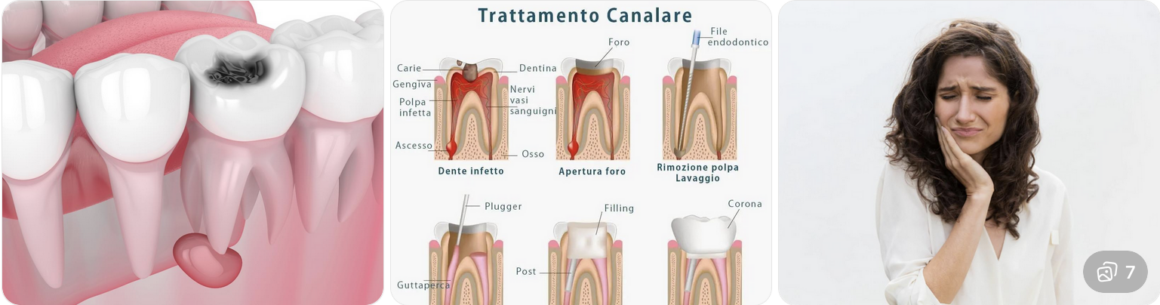

Carie Dentaria a Olbia, Sassari

Se non trattata tempestivamente, la carie può progredire fino a raggiungere la polpa del dente, causando dolore e infezioni.

I sintomi possono includere:

- sensibilità al caldo e al freddo

- dolore durante la masticazione

- macchie scure sui denti

RICCARDENT utilizza tecniche conservative per trattare la carie, preservando il più possibile il dente naturale.

Le soluzioni includono:

- otturazioni estetiche

- ricostruzioni dentali

- trattamenti canalari

La prevenzione resta fondamentale, attraverso una corretta igiene orale e controlli regolari.

Pulpite a Olbia, Sassari

Questa condizione provoca dolore intenso, sensibilità al caldo e al freddo, fastidio durante la masticazione e, nei casi più gravi, può portare a infezioni locali o ascessi dentali.

Le cause principali della pulpite includono:

- carie profonde non trattate

- traumi dentali

- lesioni da usura o abrasione dentale

- procedure odontoiatriche invasive senza protezione adeguata

La diagnosi viene effettuata da odontoiatri esperti tramite:

- esame clinico del dente

- test di vitalità pulpare

- radiografie endorali per valutare l’estensione della lesione

Presso RICCARDENT S.R.L., il trattamento della pulpite varia in base alla gravità del caso:

- pulpite reversibile: si interviene rimuovendo la causa (carie, lesioni) e proteggendo la polpa con materiali specifici

- pulpite irreversibile: si procede con la terapia endodontica (devitalizzazione), rimuovendo la polpa infiammata e sigillando il canale radicolare

L’obiettivo principale è preservare il dente naturale, prevenire infezioni e alleviare immediatamente il dolore del paziente.

Il trattamento viene completato con sedute di controllo periodiche, per assicurare che la guarigione proceda correttamente e per monitorare l’integrità della terapia endodontica.

RICCARDENT S.R.L. utilizza tecnologie avanzate come strumenti rotanti endodontici, materiali biocompatibili e sistemi di imaging digitale per garantire precisione, sicurezza e comfort.

Una gestione tempestiva della pulpite non solo riduce il rischio di complicazioni, ma contribuisce anche a mantenere una funzionalità ottimale del dente, prevenendo la perdita dentale.

Infine, i pazienti ricevono consigli personalizzati sulla prevenzione: igiene orale quotidiana accurata, controlli regolari e uso corretto di spazzolini, filo interdentale e collutori specifici.

Affidarsi a RICCARDENT S.R.L. significa scegliere professionalità, esperienza e un approccio completo alla salute dentale, con trattamenti mirati e monitoraggio costante.